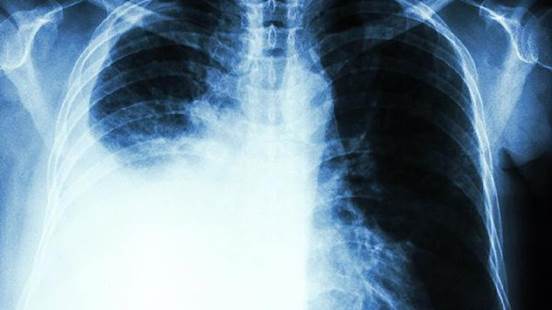

二、为什么有些人不吸烟也会得肺癌?

40岁以上人群,尤其是有吸烟史或家族病史的,建议定期做低剂量CT筛查,早期发现病变。